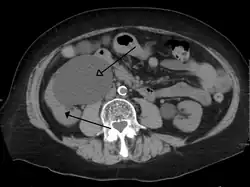

Left sided hydronephrosis in a person with an atrophic right kidney. Stent is also present (image below).

Left sided hydronephrosis, coronal view. Stent is also present.

Treatment of hydronephrosis focuses on the removal of the obstruction and drainage of the urine that has accumulated behind the obstruction. Therefore, the specific treatment depends upon where the obstruction lies.[14]

Acute obstruction of the upper urinary tract is usually treated by the insertion of a nephrostomy tube. Chronic upper urinary tract obstruction is treated by the insertion of a ureteric stent or a pyeloplasty.[13]